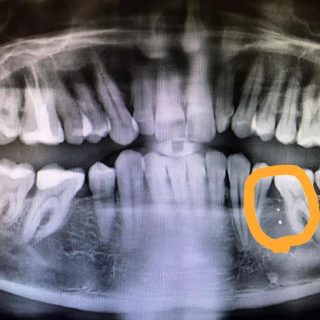

Dr. Mutter: Sadece öğrenmeniz için 10.000’den fazla hasta vakasından bir kaçı: Hasta, sağlıklı, amalgamı çıkarmak ve ucuz altın kron takılması için Bulgaristan’a gitti. Daha dönüş yolunda ilk felci geçirdi....

Amalgamlar ile asla yapılmayacaklar listelerimizi okuyunuz lütfen. Yoksa beyne cıva taşırsınız. Ve amalgamlara mutlaka smart belgeli güvenli söküm yapılmalıdır. Amalgamlar…